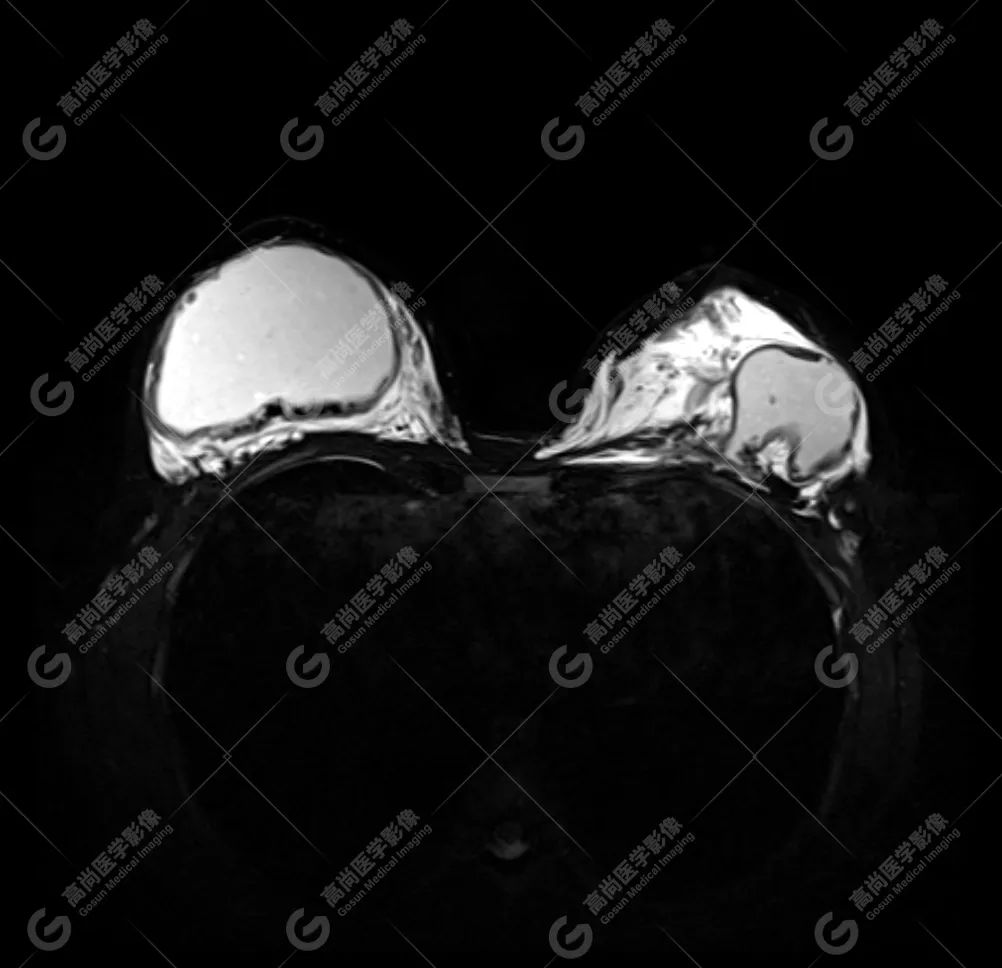

病例 4:乳腺注射物部分取出术后,后硅胶假体植入术后 3 年余

双侧假体包膜不光整,包膜下可见多发线样低信号影,左侧假体内可见「面条征」——双侧假体内包膜破裂(部分破裂)